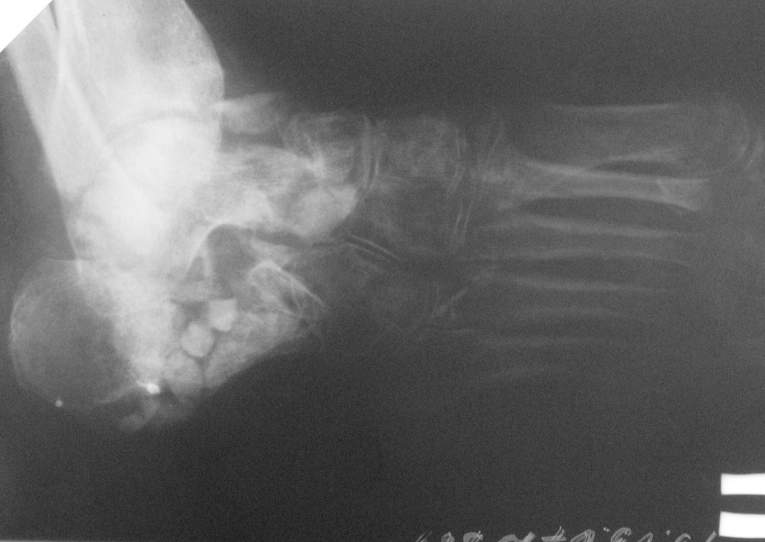

Re: Остеомиелит 4 плюсневой кости.

Приветствую. Некоторое время назад я выкладывал случай с остеомиелитом пяточной кости. Ответов я не дождался, но суть в другом.

У этой пациентки проблема была похожа тем, что свищи открывались когда она пыталась вставать на больную ногу. Была произведена санация полости пяточной кости, установлены бусы с ванкоминцином,разрешена нагрузка, пациентка показывалась через месяц, свищи не открывались с момента санации. На данный момент есть только снимки со спейсером, в следующую явку обязательно сфотографирую ногу "живьем". Можно добавить, что при санации пользуем "зеленку" с перекисью для окрашивания мертвых тканей через свищ. Бусинки лучше делать маленьких размеров - легче укладывать(особенно в костную полость), на эти грабли я уже наступил:)

Спасибо за содействие )) В моем случае я не могу точно (без фистулографии, т.к. свищ закрыт) определить уровень и объем резекции кости в соответствии с будущей (надеюсь) операцией для восстановления опороспособности стопы. Или оставшихся трех лучей будет достаточно в ортопедической обуви? Предполагается резекция средней части диафиза 4 плюсневой кости с фистулонекрэктомией.

Можно дождаться открытия свища, дело Ваше, но определяться с объемом операции, по-моему, нужно тщательно.

Не думаю, что потеря еще одного луча добавит опорности стопе. Как Вы планируете после резекции

восстанавливать длину плюсневой кости и добиваться сращения?

Предполагаемый общий (без деталей) план действий за 3тышшы км мне видится таким: 1.санация(нужна ли здесь резекция?),2. спейсер, 3.внешная или диафиксация. Можно добавить для стабильности и опорности на время лечения крепкую пластиковую лонгету на стопу. Кстати спейсер для костной полости не обязательно делать в виде бус.

Лишь бы его можно было легко удалить и в случае необходимости при отсутствии инфекции прибегнуть к костной пластике.